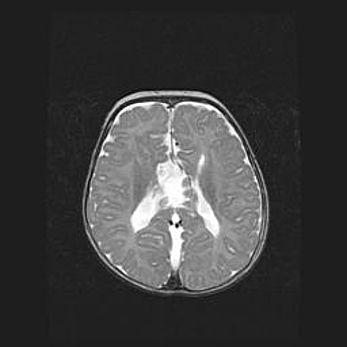

Наружная гидроцефалия с возможной атрофией височных областей.

Возраст: 28 дней

Вес: 3670 г

Пол: мужской

Окружность головы: 38 см

Срок гестации: 40 недель

Гидроцефалия головного мозга у новорожденных – это заболевание, которое характеризуется скоплением избыточного количества спинномозговой жидкости в желудочковой системе головного мозга в результате затруднения её перемещения от места выработки к месту поглощения в кровеносную систему или вследствие нарушения абсорбции. При открытой наружной форме гидроцефалии у новорожденных расширяются и переполняются субарахноидные пространства.

При нормотензивных  формах,  которые,  как  правило,  являются  следствием  перенесенных ишемических  повреждений  паренхимы  мозга,  возможно  сочетание микроцефалии  с нормотензивной гидроцефалией. В основе данных изменений лежит атрофия больших полушарий с преимущественной  локализацией  в  лобно-височных  областях.